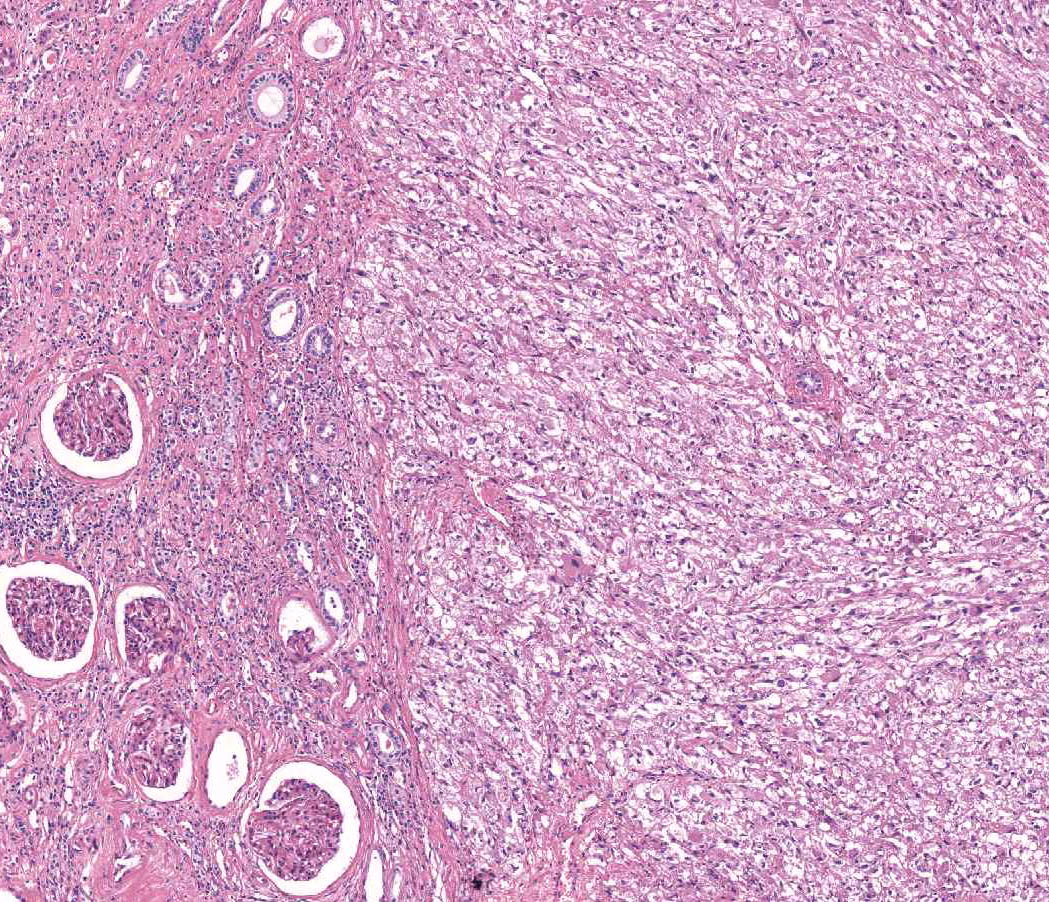

Classification of renal tumors

Case ID: 1198